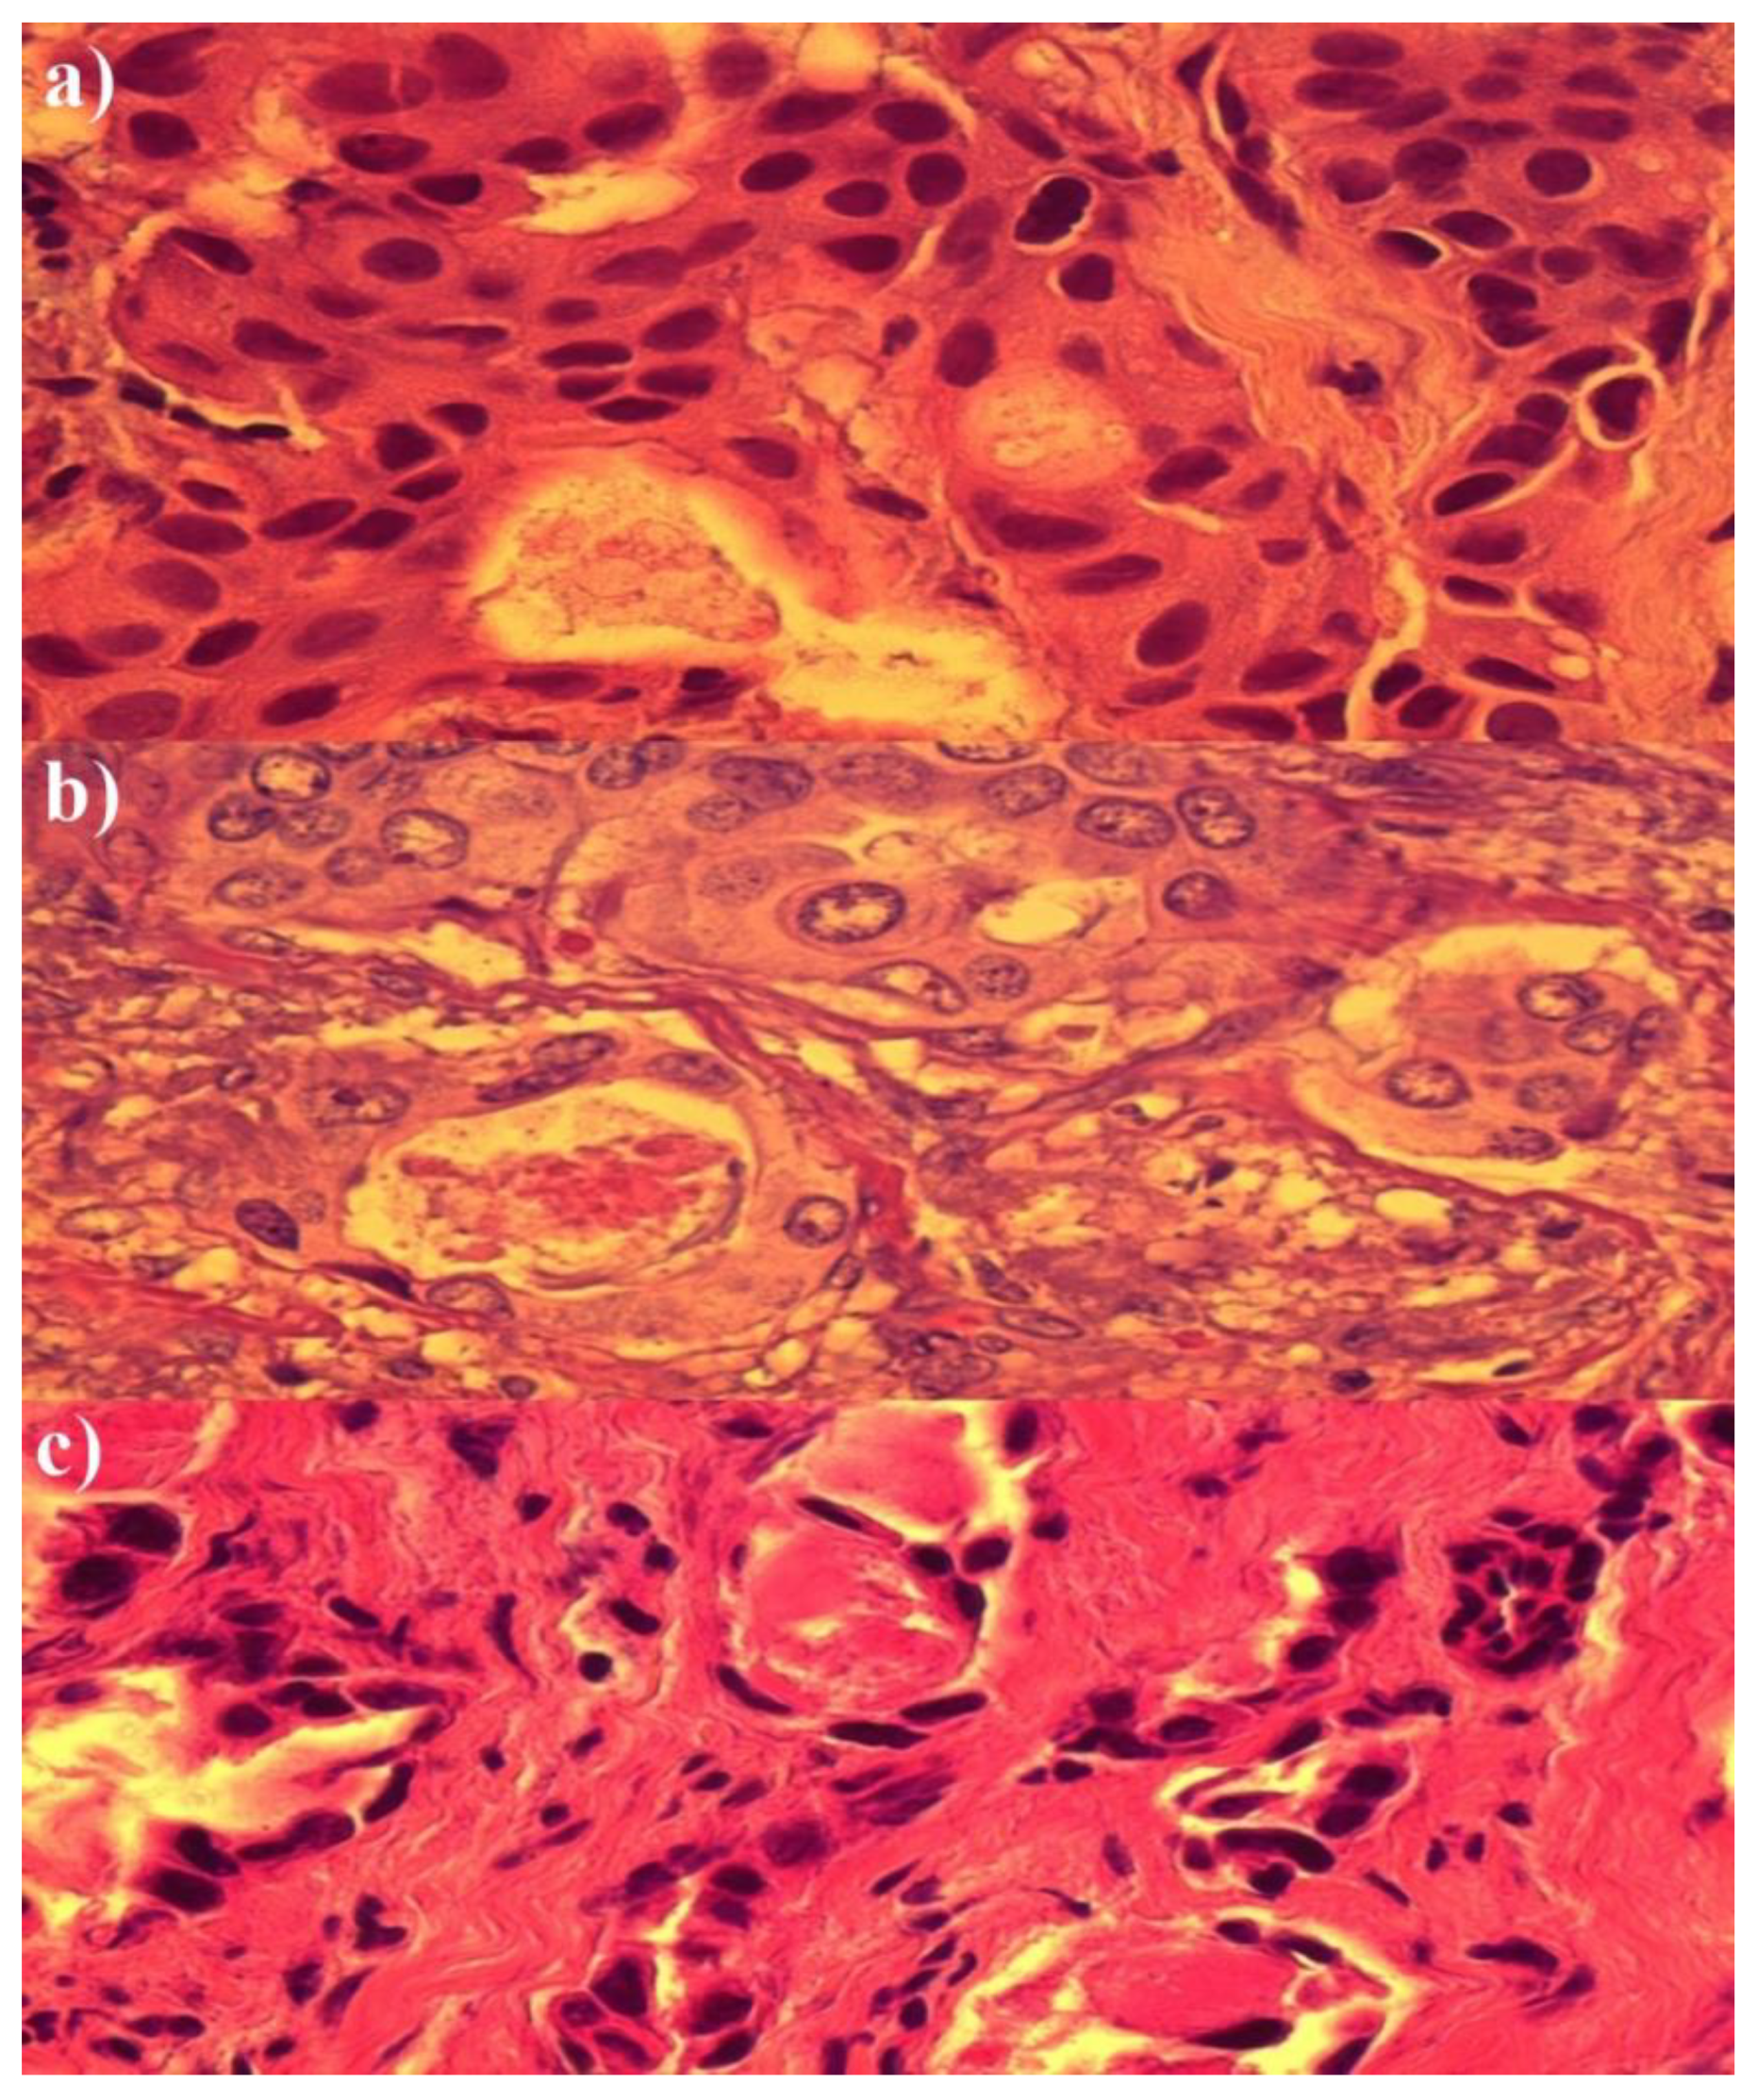

3. Results